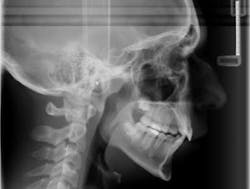

Case report A healthy 16-year-old male presents with Class II bite, an obtuse nasolabial angle, a slight, long concave profile with deficiency in the growth of the mandible, and inadequate spacing for the maxillary teeth. What are the options and talking points for this treatment plan?1. There is likely very little growth potential left in this patient, so trying to capture any remaining growth would be minimal.

3. In reference to point No. 2, orthodontic treatment planned without mandibular jaw advancement surgery in these types of cases generally will build in more dental compensations for skeletal variation (2), as the profile is compromised even more with a wider nasolabial angle, longer profile, and thus limiting the ability for any future facial profile correction.

4. The ideal treatment and recommendation would be to perform a lower jaw advancement surgery to give an ideal position of skeletal and dental components. Worms et al. reported that the total interrelationships of surgical and orthodontic contributions are in the best care and interest of the patient long term. (2)

5. It can be argued that mandibular jaw advancement surgery could, down the road, cause TMJ concerns/issues or create a dual bite. A study done by Mihalik et al. reported that orthodontics-only patients reported fewer functional or TMJ problems than did the surgery patients, but patients who had their mandibles advanced were significantly more positive about their dentofacial images. (1) This is an important concept to remember — beauty is in the eye of the beholder!

It could be concluded with the aforementioned talking points that there is not a right or wrong way to proceed in cases like this. Some options are better than others, but this is the take-home point: If a Class II patient (as presented herein) does have the upper 4’s removed, it exacerbates the existing profile and limits virtually any potential for a correction of profile in the future. It is, therefore, vital to discuss all risks, benefits, complications, and alternatives so the patient can make the best decision possible. Assuming no regard to cost or possible complications, the mandibular advancement would be considered by most to be the preferential treatment in this case, as it resolves the core problem — mandibular deficiency. In this case, the patient was not willing to undergo a surgical procedure at this time, so the treating orthodontist advised the family against the removal of maxillary teeth in order to preserve facial profile and allow for possible future mandibular advancement procedure.